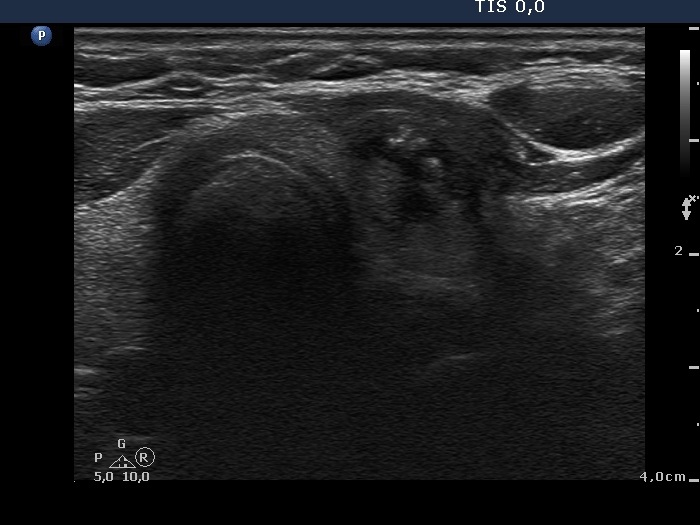

Ultrasonography. The right lobe was echonormal and contained several small, insignificant lesions. There was a hypoechogenic, irregularly shaped mass in the lower half of the left lobe. The lesion had a rigged, echonormal core which showed bright hyperechogenic granules. There were multiple incomplete acoustic shadows dorsal to the lesion which was avascular.